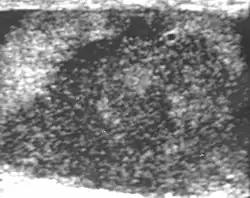

Primary leukemia of the testis is rare. However, due to the presence of blood-testis barrier, chemotherapeutic agents are unable to reach the testis, hence in boys with acute lymphoblastic leukemia, testicular involvement is reported in 5% to 10% of patients, with the majority found during clinical remission. The sonographic appearance of leukemia of the testis can be quite varied, as the tumors may be unilateral or bilateral, diffuse or focal, hypoechoic or hyperechoic. These findings are usually indistinguishable from that of the lymphoma [Fig. 9].

Fig. 9. Leukemia. Diffuse hypoechoic infiltrative lesions are seen involving the whole testis, indistinguishable from that of the lymphoma.